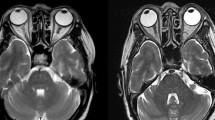

A total of 84 patients were included in this research, with a mean age of 62.24 ± 14.52 years and male-to-female ratio of 43:41. The pathological types comprised benign orbital lymphoproliferative tumours (26/84, 31%, mean age 59.31 ± 10.4 years, male-to-female ratio of 16:10) and malignant orbital lymphomas (58/84, 69%, mean age 63.55 ± 15.93 years, male-to-female ratio of 27:31). The most common symptoms in benign and malignant OLPDs were palpable mass and eyelid swelling. Typically, malignant orbital lymphoma masses exhibited low signal intensity on T1-weighted imaging (T1WI), whereas benign lymphoproliferative tumours commonly demonstrated iso-intensity on T1WI. Notably, the expression of cluster of differentiation 3, 5, 10, 23, 43, and human immunoglobulin light chain lambda demonstrated statistically significant differences between the benign and malignant OLPD groups.